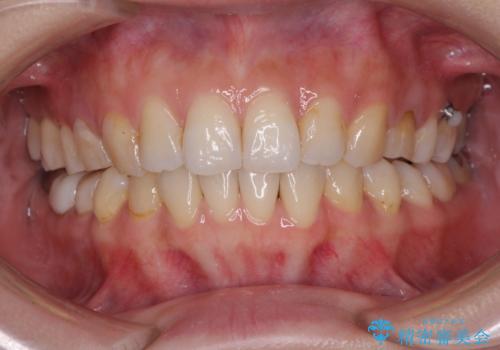

- 失活により変色した歯と不揃いな口元を気にして来院された患者様です。

口元をインビザラインにより歯列を整え、その後に失活している奥歯をオールセラミッククラウンにて補綴治療することとしました。

長時間のマウスピース装着と、患者様自身でのゴムかけに協力いただき、自然な口元に仕上げることができました。

気になっていた変色した歯もオールセラミッククラウンで本物の歯のようになり、患者様には大変満足していただきました。